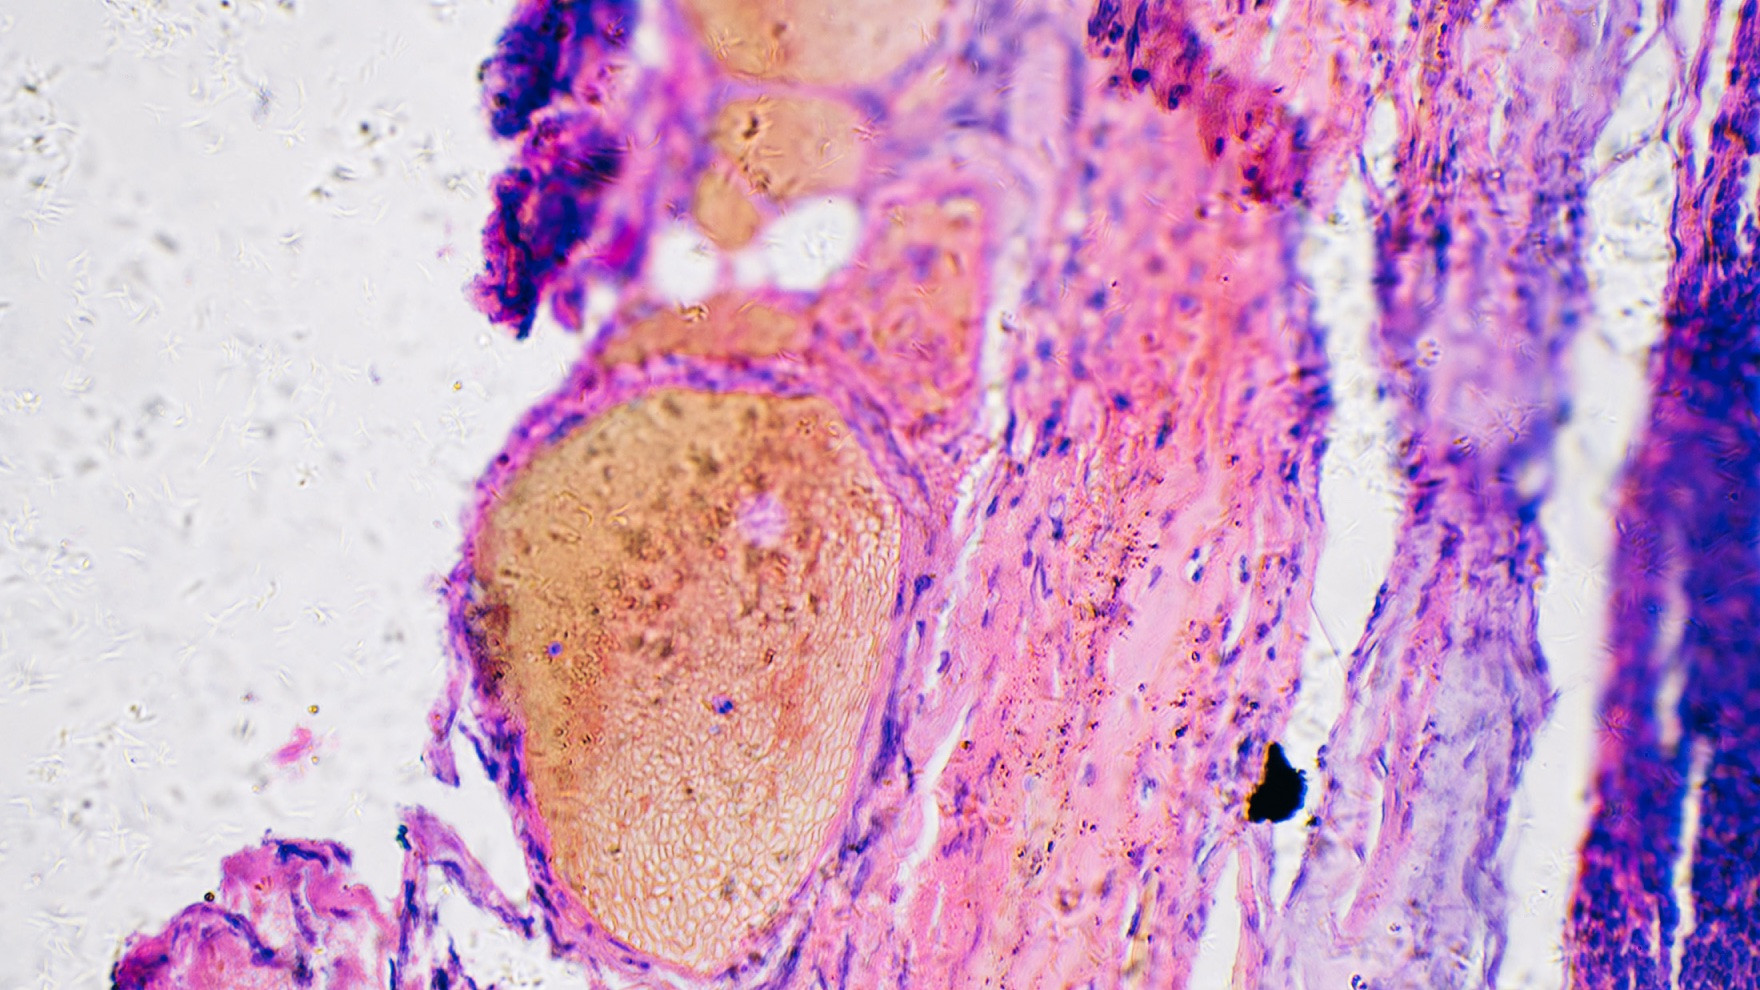

Targeted Therapy

Nanodiamonds allows for precise targeting of specific cells, tissues, and organs in the body. With minimally invasive procedures, we can reduce risk and achieve faster recovery times. -

Early Detection

We can detect disease biomarkers with high sensitivity and specificity, enabling early diagnosis of the most challenges diseases such as cancer, infectious diseases, and neurodegenerative disorders. -

Immuno-Oncology

Targeted nanodiamond-mediated delivery of Camelidae (Alpaca) derived Nanobodies for therapeutics in immunology and immuno-oncology. -